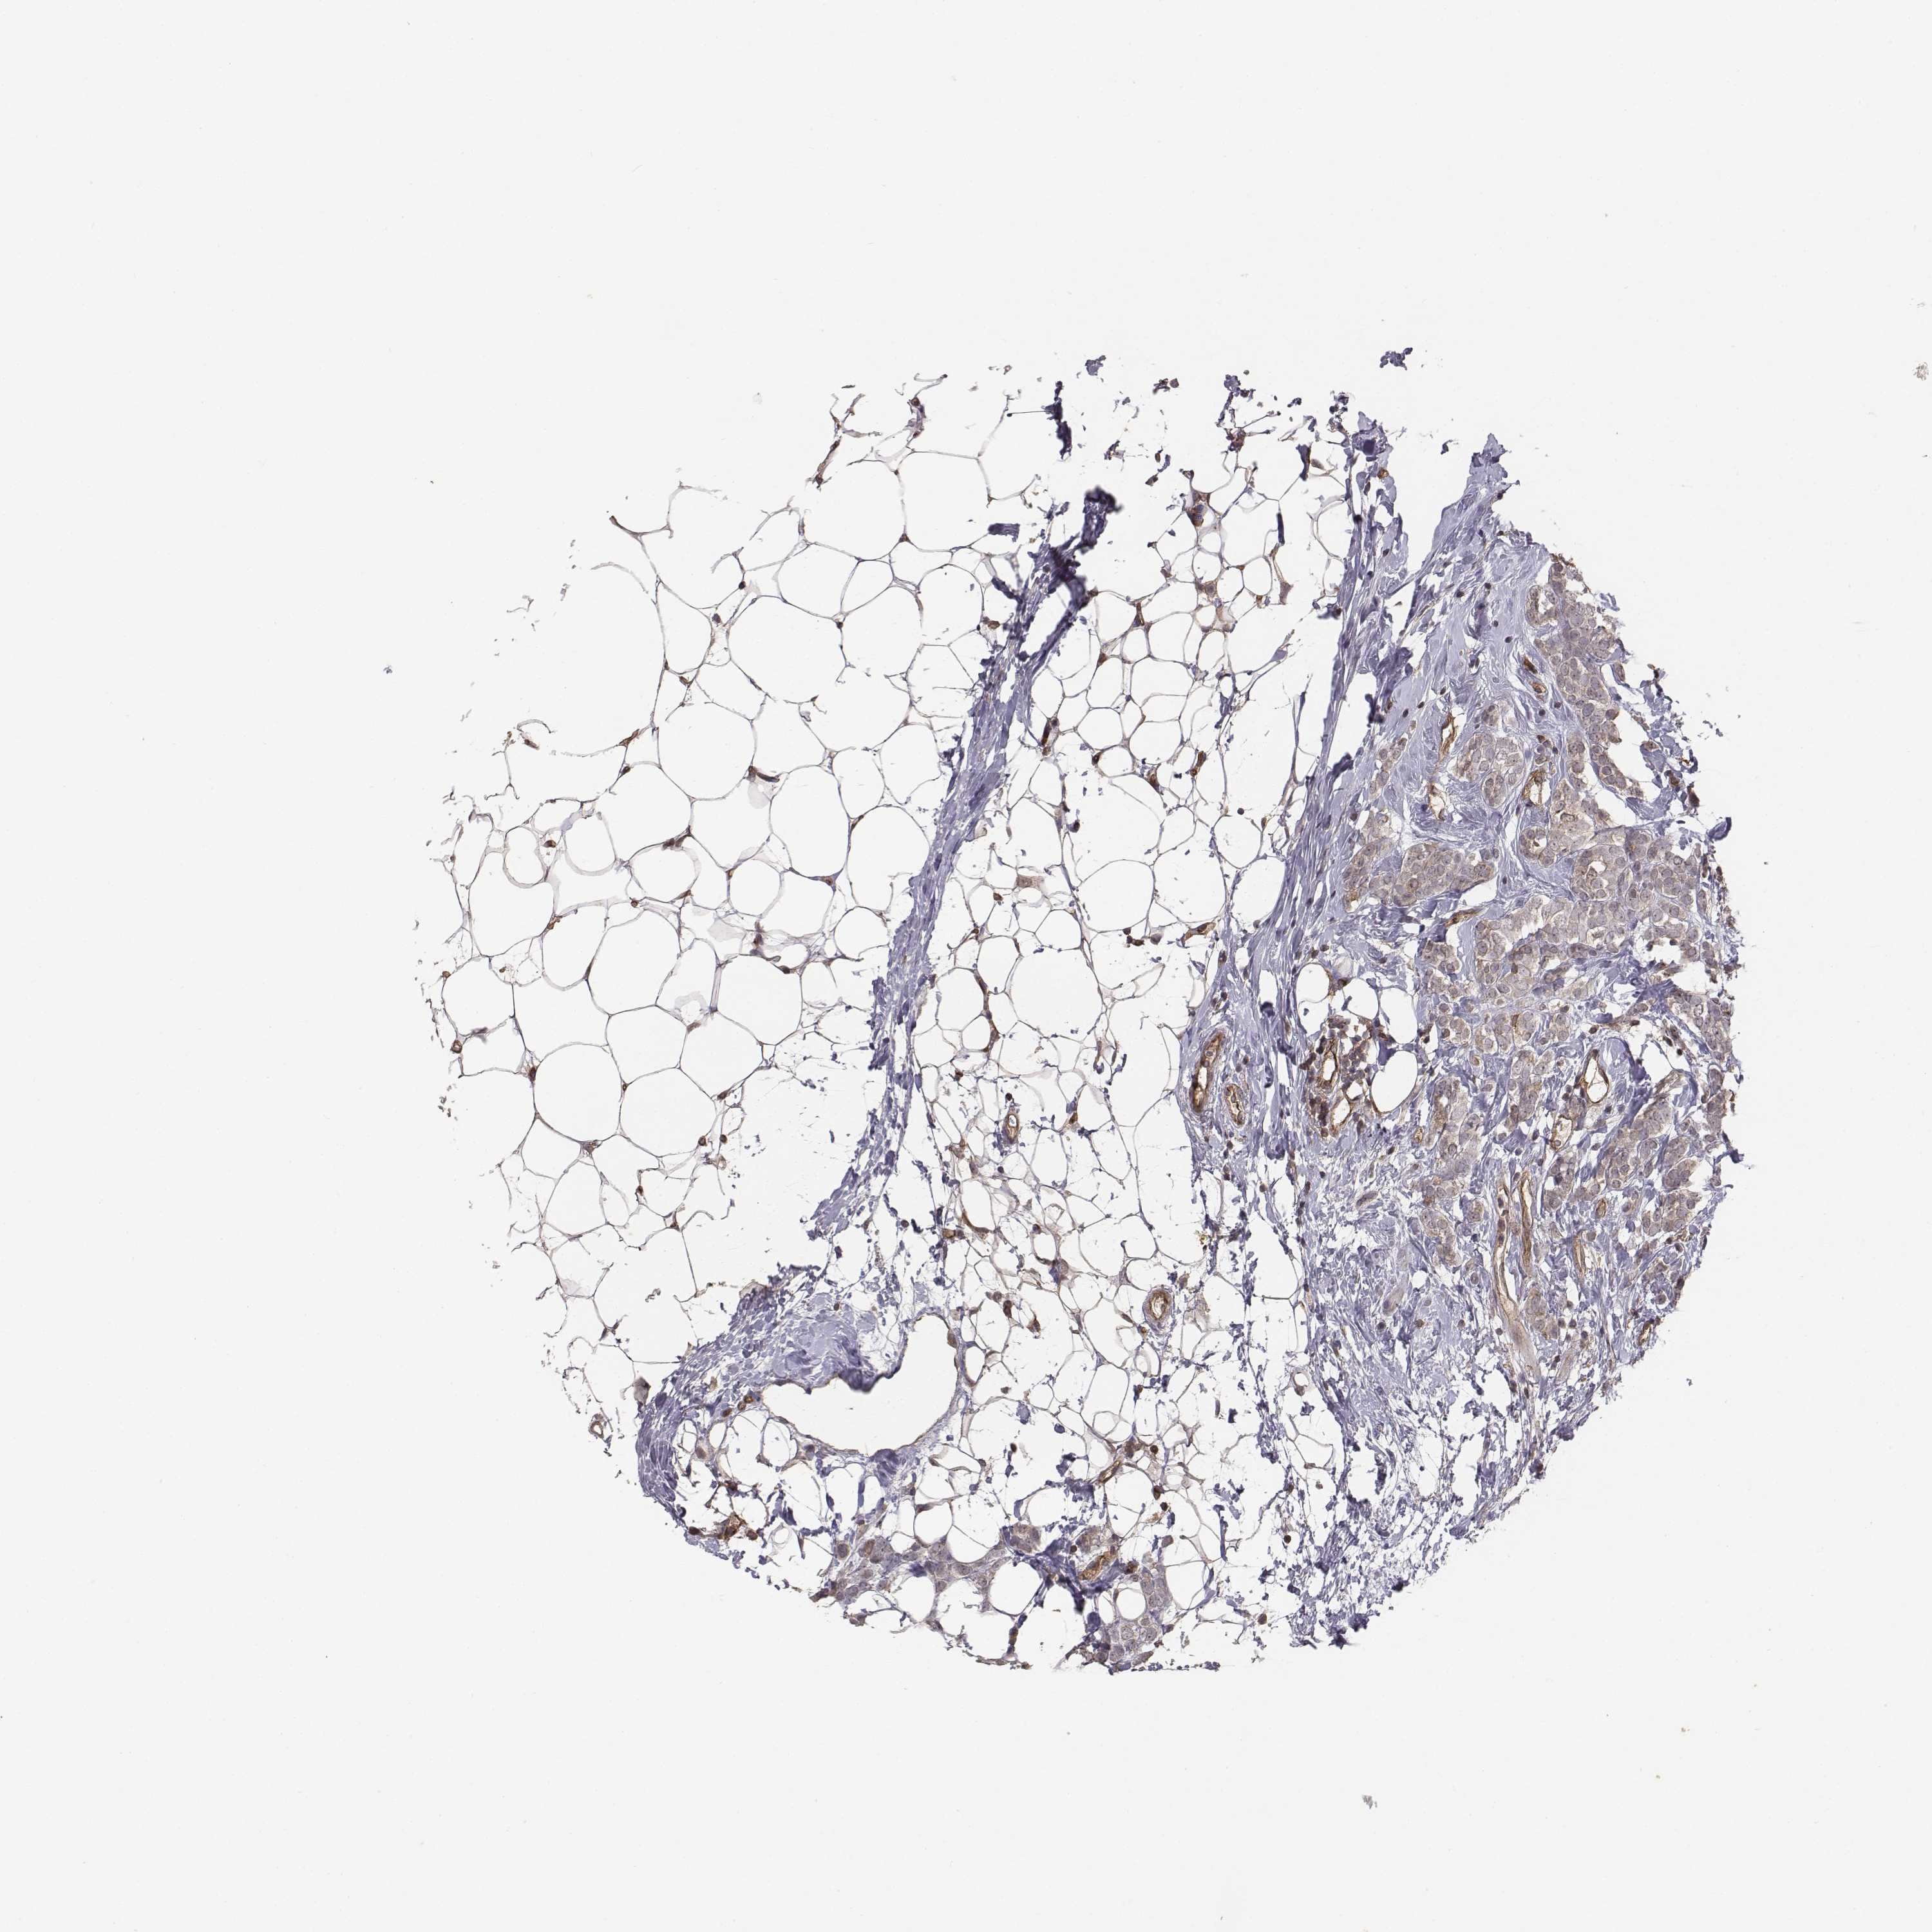

BRCA TCGA BRCA VALIDATION PROTEIN EXPRESSION